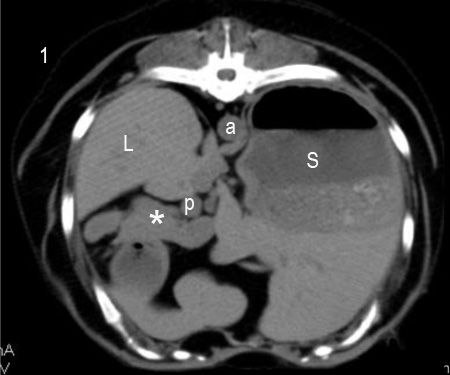

Because of the highly vascular nature of insulinomas, these tumors typically show intense enhancement (hyperattenuation) in the arterial phase, compared with normal pancreatic parenchyma, with similar enhancement to normal pancreatic tissue in the venous phase.7,8 A more recent paper suggested that the pattern of enhancement may be more variable, with hypoattenuating lesions seen as commonly as hyperattenuating lesions in at least one phase.9 While further studies including larger numbers of cases are needed to better define the CT imaging characteristics of insulinomas, CTA remains the best imaging modality for the identification and staging of these tumors (Figure 2).

Figure 2. Transverse CT images of the dog in this case at the level of the pancreatic body and left limb, obtained pre-contrast (1), and in the arterial (2) and portal (3) phases of enhancement (1 ml/lb of iodinated nonionic contrast medium, 300 mg iodine/ml). A small, 1-cm nodule is visible ventral to the portal vein in the arterial phase of enhancement (arrows), but not pre-contrast or in the portal phase. This nodule was surgically resected and confirmed to be an insulinoma on histopathologic examination. L: liver; S: stomach; a: aorta; p: portal vein; C: caudal vena cava; asterisk (*): pancreas.References